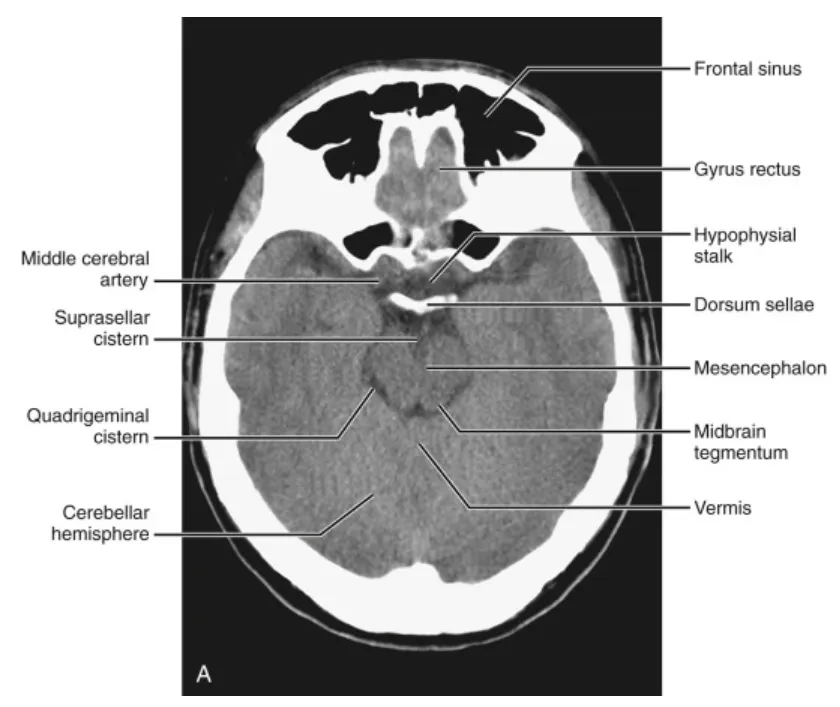

(3) Above the fourth ventricle

중심부에는 midbrain가 suprasellar cistern, ambient cistern, 그리고 quadrigeminal cistern에 의해 윤곽이 그려져 나타납니다. suprasellar cistern에는 ICA, ACA과 MCA, optic chiasm, infundibulum, mammillary bodies, 그리고 basilar artery의 상부가 포함되어 있습니다. 중뇌의 측면에는 측두엽(temporal lobes)이 있으며, 여기서 구상돌기(uncus), 편도핵(amygdaloid nucleus), 그리고 해마형성체(hippocampal formation)를 확인할 수 있습니다. 측두각(temporal horn)은 이 수준에서 측두엽 중간에서 볼 수 있습니다. 전두개와(anterior fossa)에서는 전두엽(frontal lobes)이 실비우스열(sylvian fissure)에 의해 측두엽과 분리됩니다. 전두엽의 가장 하부가 이 수준에서 보입니다. 후두개와(posterior fossa)에서는 실비우스수도(aqueduct of Sylvius)가 중뇌 뒤쪽에 존재합니다. 소뇌의 상부 표면(superior cerebellar surface)이 보이며, 두 반구가 상부 소뇌충부(superior vermis)에 의해 분리됩니다.